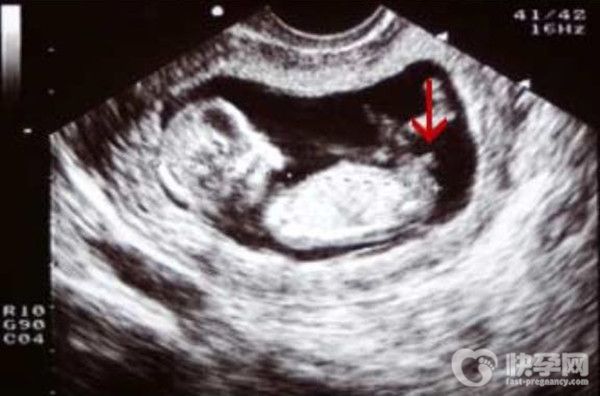

但是在四维彩超也能看出胎儿的性别,100%准确的方法其实是这个:nub点看男女。详细办法如下:

如果nub点的角度大于30度,说明是男孩,如果不是30度,说明是女孩。

如果nub点倾斜的角度特别陡,屁股向上翘,也可以说明孩子是男孩,反之,就是女孩;